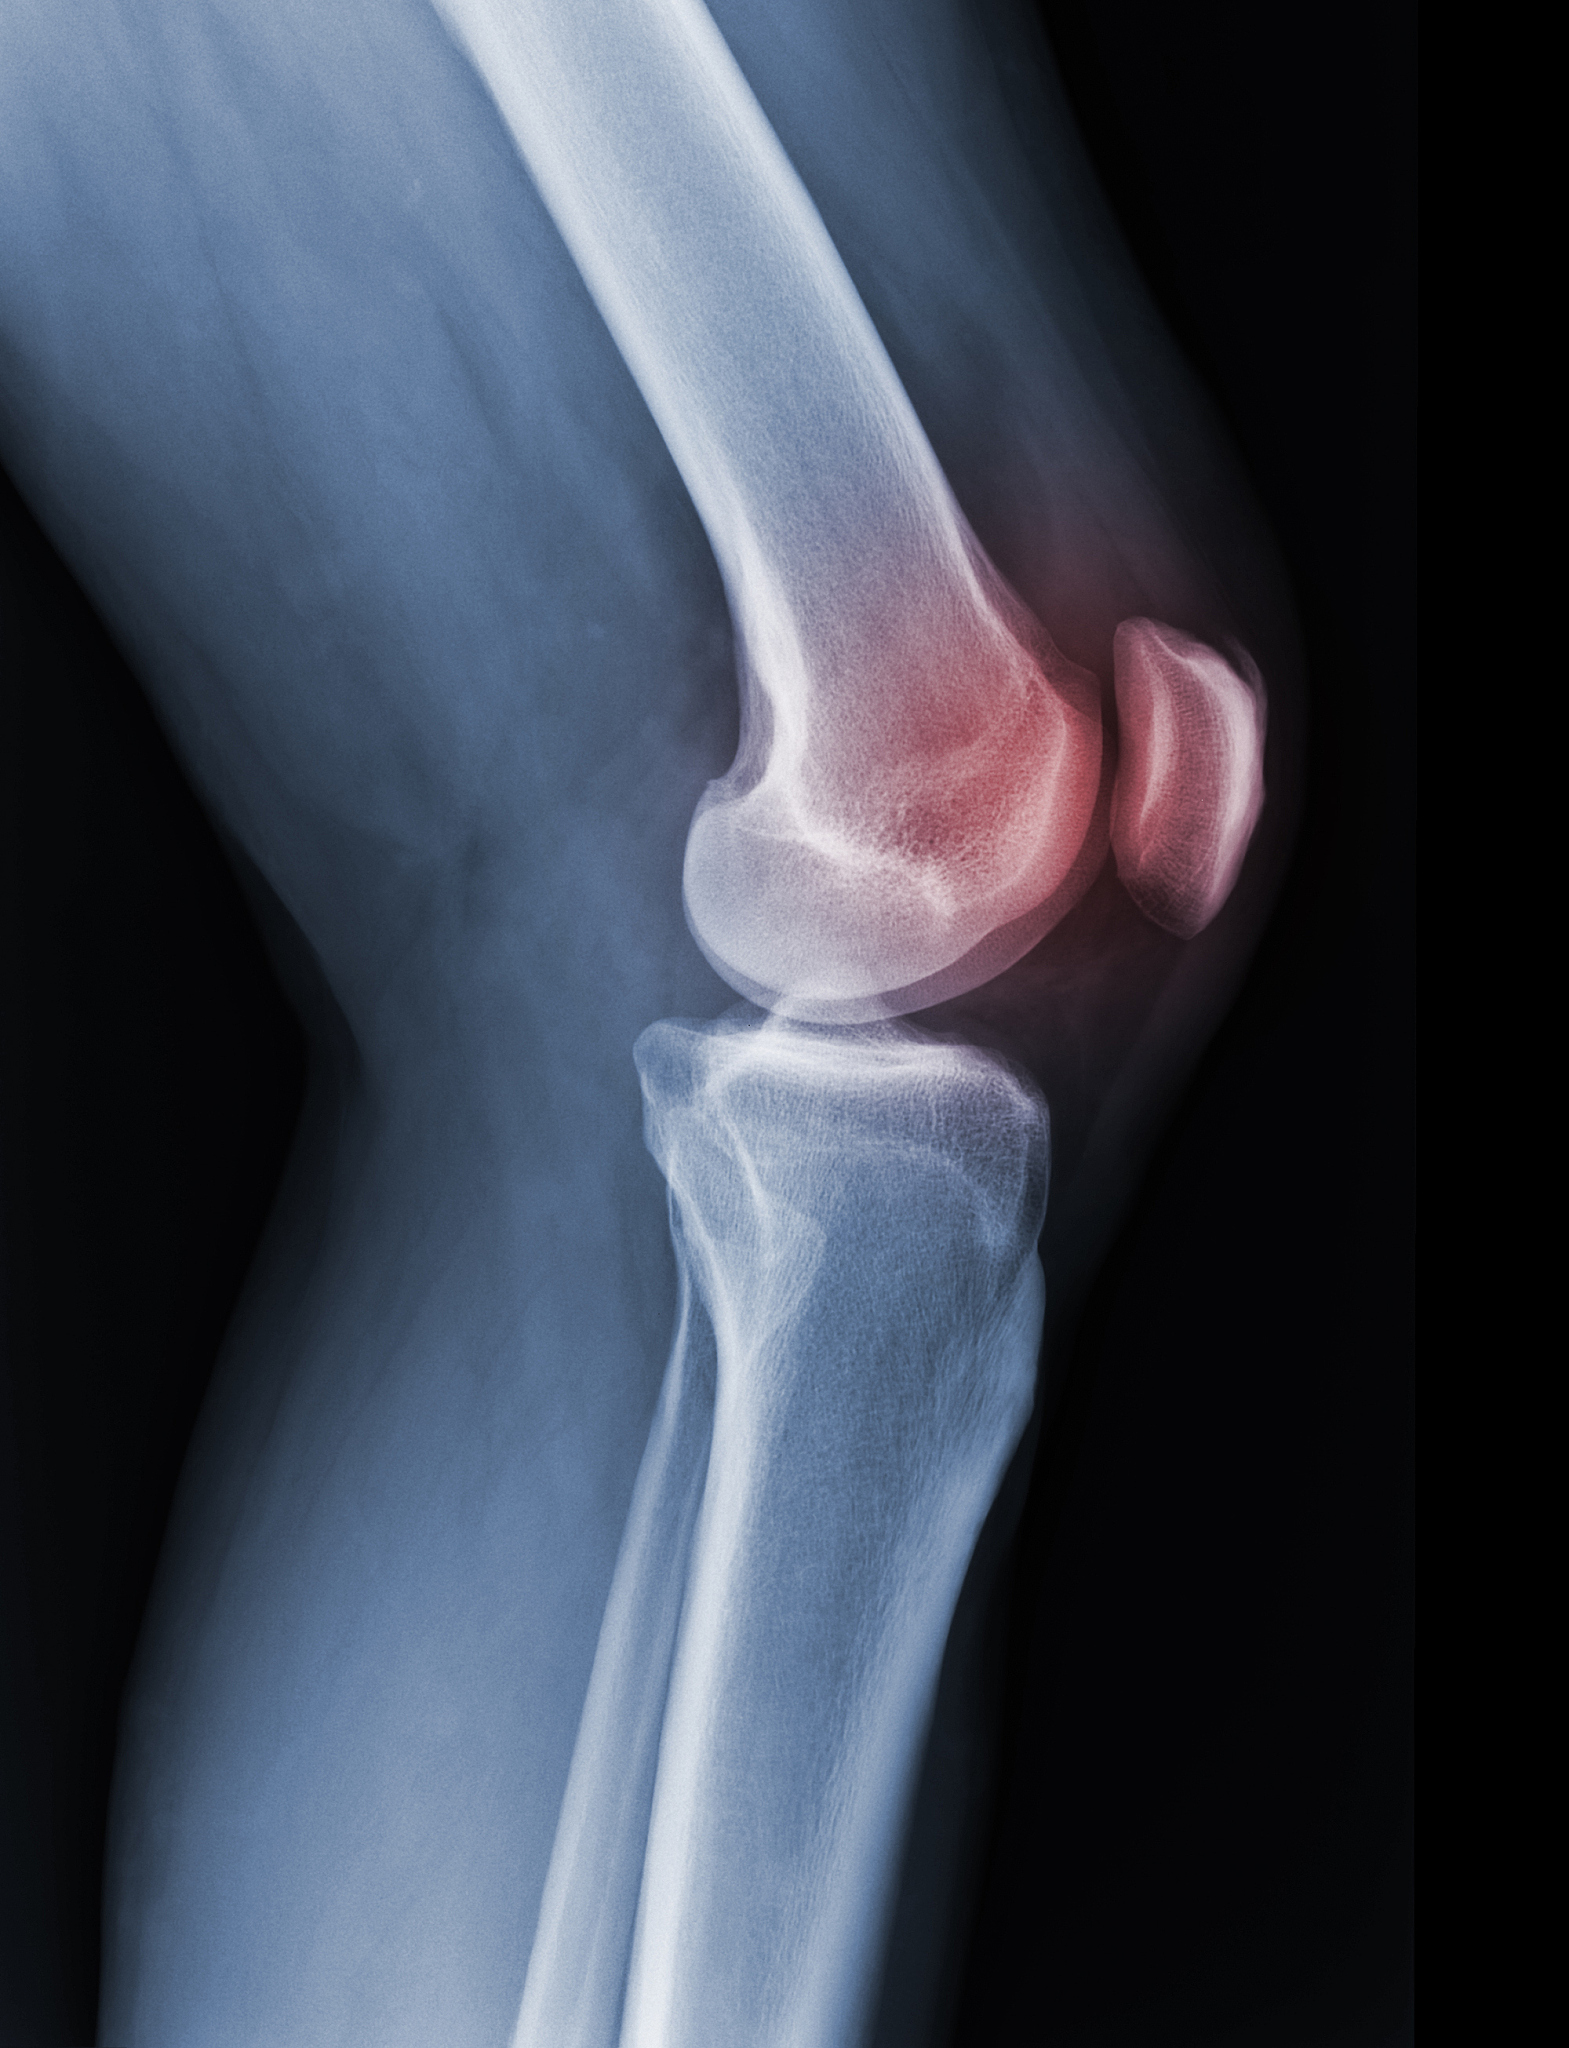

滑囊炎是指滑囊发炎,通常会导致膝盖疼痛、肿胀和活动受限。如果滑囊炎严重,可能会导致膝盖骨头摩擦,产生摩擦声音。这种声音被称为关节摩擦音,可能是由于滑囊炎引起的软组织炎症导致关节内液体减少,从而使骨头之间的摩擦增加。

如果出现这种情况,建议及时就医,进行详细的检查和诊断。医生可能会建议进行X光、MRI或关节镜检查,以确定具体的病因和治疗方案。治疗滑囊炎的方法通常包括休息、物理治疗、药物治疗和手术等。